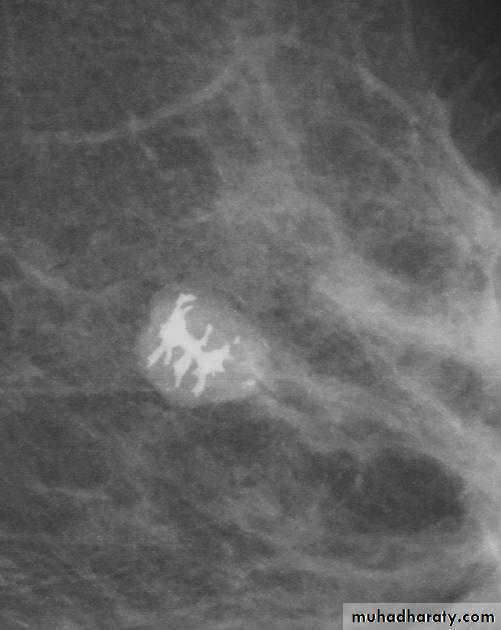

Micro calcifications

Micro calcifications are tiny specks of calcium in the breast. Micro calcifications seen on a mammogram are of more concern than macrocalcifications, but they do not always mean that cancer is present. The shape and layout of microcalcifications help the radiologist judge how likely it is that cancer is present.

In most cases, the presence of microcalcifications does not mean a biopsy is needed. But if the microcalcifications have a suspicious look and pattern, a biopsy will be recommended. (During a biopsy, the doctor removes a small piece of the suspicious area to be looked at under a microscope. A biopsy is the only way to tell if cancer is really present.)